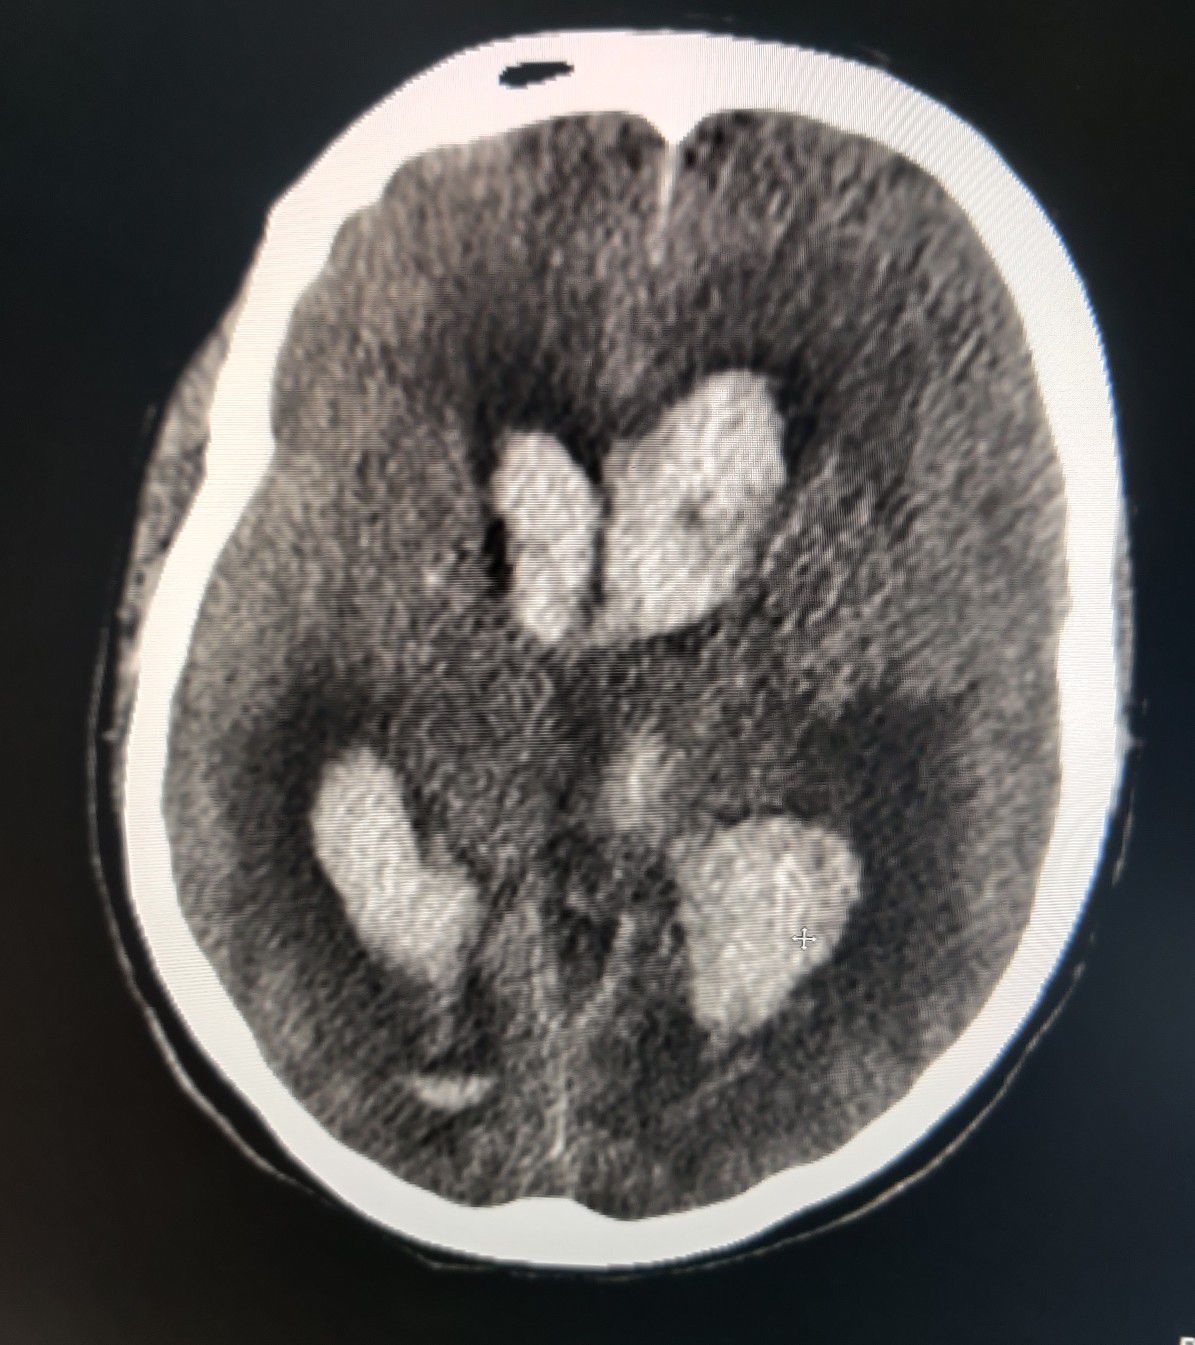

B/L Hemorrhagic CVA including lateral ventricles and 3rd Ventricle

Stroke

Cva

Hemorrhagic